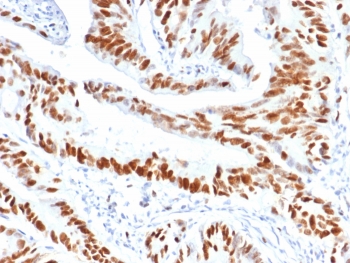

Immunohistochemistry analysis of MCM3 antibody (clone MCM3/6706) in human colon carcinoma tissue. Formalin-fixed, paraffin-embedded human colon carcinoma shows strong nuclear brown staining in malignant epithelial cells, consistent with MCM3 expression in actively proliferating tumor cells, while surrounding stromal cells display weaker or focal nuclear signal. Heat-induced epitope retrieval was performed by boiling tissue sections in pH 9 10mM Tris with 1mM EDTA for 20 min followed by cooling prior to staining.

Minichromosome maintenance complex component 3 plays a critical role in establishing the pre-replication complex, ensuring that DNA replication occurs once per cell cycle. Following origin licensing, the MCM2-7 complex cooperates with CDC45 and the GINS complex to form the CMG helicase, the central enzymatic machinery driving replication fork progression. Nuclear localization of MCM3 reflects its function in chromatin-associated replication control. In immunohistochemical analysis, MCM3 antibody typically produces distinct nuclear staining in actively dividing epithelial, lymphoid, and progenitor cell populations, while differentiated or quiescent cells demonstrate minimal signal.